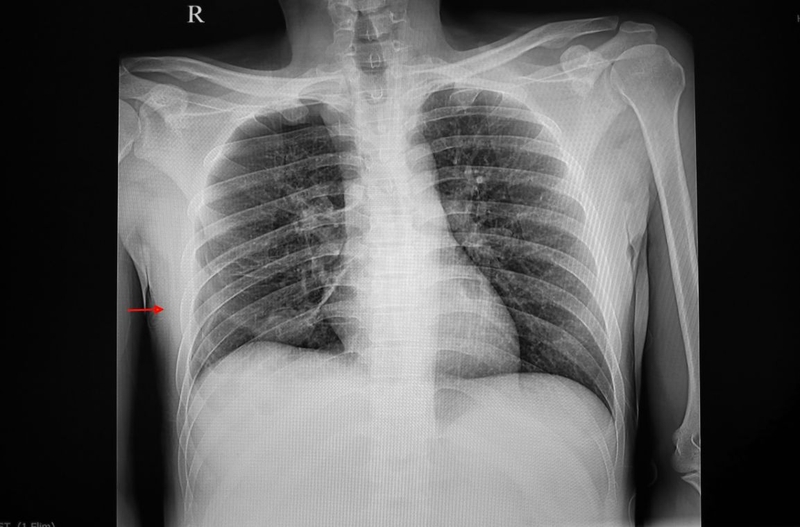

Chụp X quang tràn khí màng phổi là kỹ thuật quan trọng trong phát hiện, chẩn đoán, đánh giá tình trạng tràn khí màng phổi. Căn cứ vào phim chụp, các bác sĩ có thể phân loại bệnh, từ đó chỉ định phương pháp điều trị phù hợp.

Chụp X quang là kỹ thuật sử dụng chùm tia X năng lượng cao chiếu xuyên qua các cấu trúc bên trong cơ thể người. Chụp X quang phổi thường được chỉ định để phát hiện, đánh giá các bệnh lý về phổi, trong đó có tràn khí màng phổi. Căn cứ vào thông tin và hình ảnh X-quang tràn khí màng phổi thu được, các bác sĩ có thể phát hiện, chẩn đoán, đánh giá, phân loại bệnh. Đồng thời, kỹ thuật chẩn đoán hình ảnh này cũng giúp bác sĩ phát hiện thêm các bất thường khác ở phổi hay ở cơ quan lân cận nếu có.

Ảnh phim chụp X quang tràn khí màng phổi thể hiện:

Không phải lúc nào chẩn đoán tràn khí màng phổi bằng chụp X quang cũng giúp bác sĩ kết luận bệnh nhân chóng và chính xác. Chẩn đoán bệnh có thể bị nhầm lẫn với các kén khí lớn. Có những bệnh nhân đã bị tràn khí màng phổi nhưng hình ảnh trên phim X quang chưa thể hiện. Khi đó, bác sĩ có thể chỉ định người bệnh chụp CT phổi để chẩn đoán bệnh nhanh chóng, chính xác nhất.